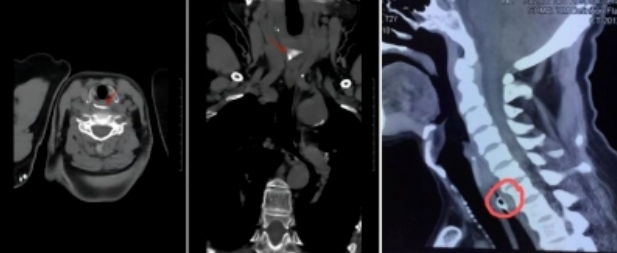

3.检查方法

目前临床的主要检查方法有:间接喉镜/纤维喉镜检查除外喉部卡顿;颈部X线片/颈胸部CT检查;食管镜或胃镜检查。